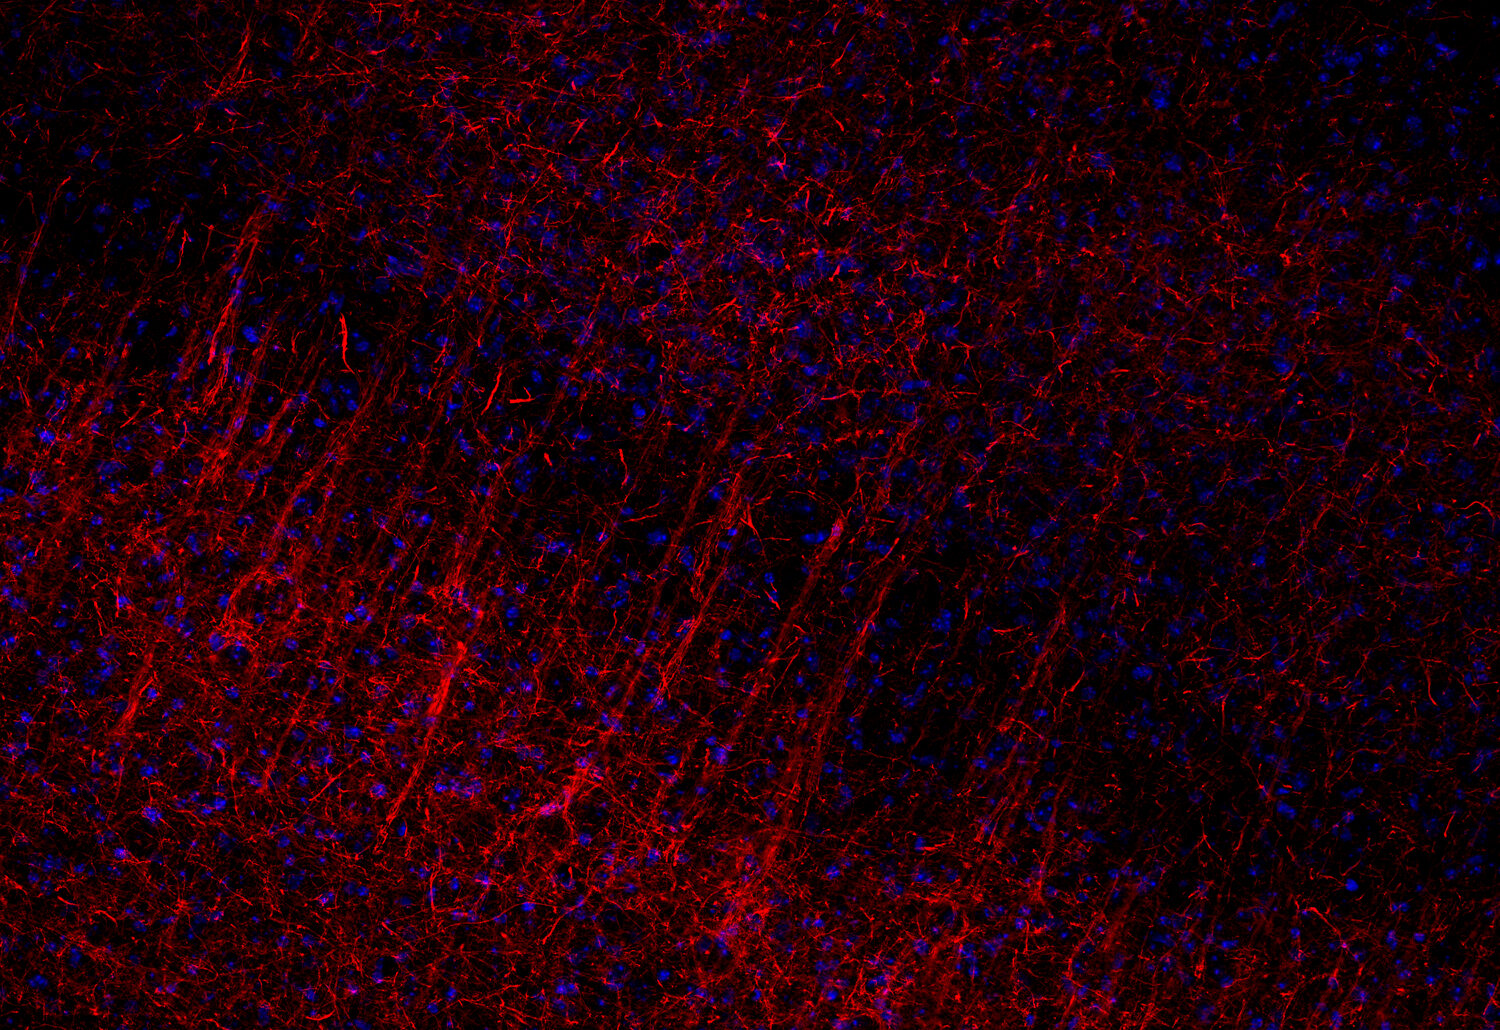

ICC: 1 : 500 up to 1 : 1000 gallery

IHC: 1 : 500 up to 1 : 1000 gallery

IHC-Fr: 1 : 500 gallery

Immunocytochemistry (ICC) on 4% PFA fixed cells. Immunoreactivity is usually revealed by fluorescence. Some antibodies require special fixation methods. For details, please refer to the “Remarks” section.

Immunohistochemistry (IHC) on 4% PFA perfusion fixed tissue with 24h PFA post fixation. Immunoreactivity is usually revealed by fluorescence or a chromogenic substrate. Some antibodies require special fixation methods or antigen retrieval steps. For details, please refer to the ”Remarks” section.

Neurofilaments (NFs) are intermediate filaments essential for providing structural support to neurons, particularly within axons. They play a crucial role in maintaining axonal diameter, which directly influences nerve conduction velocity (1). Neurofilaments are composed of three primary subunits - NF-L (light), NF-M (medium) and NF-H (heavy) – along with an NF-associated protein. In the adult central nervous system (CNS), α-internexin serves as the fourth neurofilament subunit, whereas in the peripheral nervous system (PNS), peripherin takes on this role (2).

Beyond their structural function, neurofilaments are also valuable biomarkers in both research and clinical settings. They are widely used in immunohistochemistry to stain and visualize axons, particularly in peripheral nerves and the CNS. Increased levels of neurofilament proteins in cerebrospinal fluid (CSF) or blood are strongly associated with neurodegenerative diseases, such as amyotrophic lateral sclerosis (ALS), multiple sclerosis (MS), and Alzheimer’s disease (3). In peripheral nerve studies, neurofilament staining is often combined with other markers, such as S100, to provide a more comprehensive assessment of nerve structure and pathology (4).